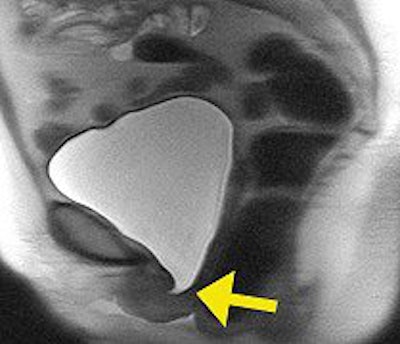

![]() |

| Strain imaging steady-state fast spin echo (SSFSE) of urethra mobility and bladder neck competence assessment. Note hypermobility of urethra that assumed horizontal position and bladder neck funneling (arrow). Image courtesy of Dr. Katarzyna J. Macura, Ph.D., Johns Hopkins University. |

With ISD, MRI predicted four cases with 100% sensitivity and specificity, Macura said. Specific findings included shortening in the urethra and bladder neck funneling. Two cases of mixed incontinence were diagnosed with 100% accuracy, she added. Finally, the researchers found a high correlation between VLPP and sphincter muscle length, Q-tip mobility, and hypermobility angle on MRI, and between MUCP and posterior striated muscle thickness of the midurethra.